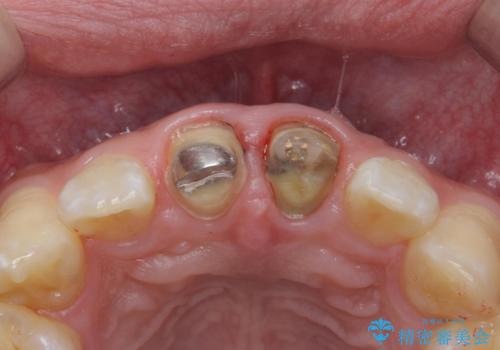

- 前歯のかぶせ物の変色を主訴に来院された患者様です。

根管治療からのやり直しはご希望されませんでした。

今回はe-maxクラウンで修復していきます。